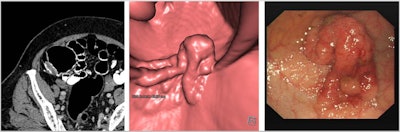

CT colonography (CTC) is a highly sensitive, well-tolerated test for the diagnosis of colorectal cancer and polyps, they explained. Colorectal cancer is the fourth most common cancer in the U.K., with over 42,300 cases a year. Currently, more than 100,000 CTC examinations are conducted each year in England alone, and this figure is increasing each year.

When performed to the highest quality, CTC has excellent diagnostic accuracy for clinically significant neoplasia -- i.e., colorectal cancer and advanced neoplasia -- in both symptomatic and screening populations. But unlike colonoscopy, substantial variations in practice exist in the U.K. and internationally, they added.